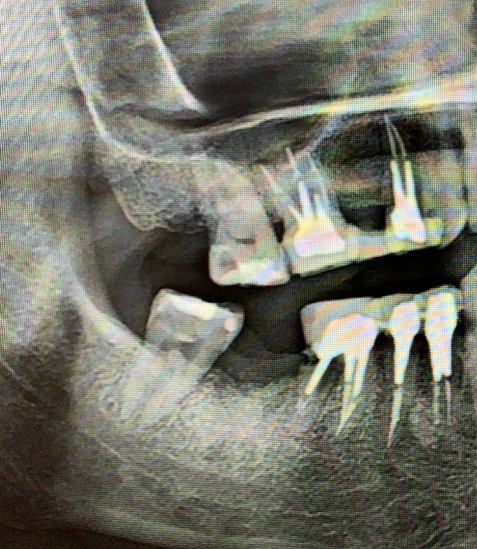

Январь 2023. Произошел спор с пациентом, который 4 месяца назад удалил зубы в городской поликлинике, где ему разворошили всю кость и он был очень удивлен, почему мы не сможем сходу установить импланты без наращивания. Этой ситуацией хотелось с кем-то поделиться, причем с тем, для кого это не рутина. Я вспомнил про свои посты. И меня понесло. Начал писать статьи одну за другой. И в какой-то момент я заметил, что чем больше я пишу, тем больше народ начинает задумываться о своем здоровье. Люди стали засыпать меня вопросами, я по мере возможности отвечал, иногда совсем поражался тем, насколько люди у нас не просвещены в этом плане. Стало поступать множество призывов помочь, просили персональной консультации.

Кидаем снимки, если есть.

Если есть КТ, то кидаем на почту vadbel1310kt@yandex.ru В теме письма указываем ваш никнейм телеграме, чтобы я мог понять кто это прислал, посмотреть и ответить.